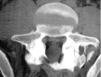

El osteoma osteoide es un tumor osteoblástico benigno que se observa con mayor frecuencia en hombres y suele aparecer entre los 7 y los 25 años de edad. La clínica más habitual es dolor de predominio nocturno que mejora con antiinflamatorios no esteroideos (AINE). Su aparición es más frecuente en huesos largos, sin embargo puede asentar también en la columna vertebral, sobre todo lumbar. La región de la vértebra más comúnmente afectada es el arco posterior. El diagnóstico se confirma mediante al análisis anatomopatológico, siendo la tomografía computarizada (TC) la técnica de imagen de elección. Presentamos dos casos de osteoma osteoide espinal atípicos. En ambos el diagnóstico inicial se realizó mediante TC y gammagrafía ósea.

Osteoid osteoma is a benign osteoblastic tumor that is most frequently observed in men and generally appears 7 and 25 years of age. The most common clinical manifestation is pain which increases at night and is relieved with non-steroidal anti-inflammatory drugs (NSAIDs). Its most common appearance is in the long tubular bones, however, we can also find it in the spine, most frequently in lumbar spine. Vertebral osteoid osteomas usually arise from the posterior elements. Computed tomography (CT) is the imaging technique of choice, although diagnosis is confirmed by pathology studies. Two cases of atypical spinal osteoid osteoma are presented. In both of them, CT and bone scintigraphy were helpful in obtaining the final diagnosis.